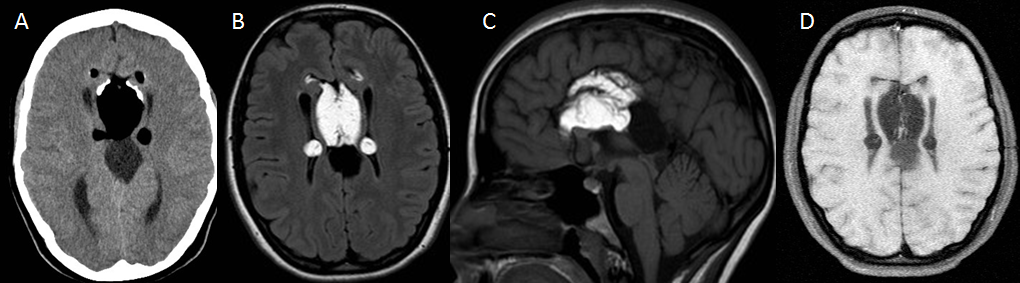

Mujer de 37 años con amenorrea que ingresa por poliuria y polidipsia. Antecedentes de anemia hemolítica no inmune, esplenectomizada. En tratamiento con metformina.

Depósito de hierro en la hipófisis secundario a hemocromatosis secundaria produciendo un hipogonadismo hipogonadotrófico.

La hemocromatosis secundaria es una enfermedad caracterizada por el depósito de hierro en el hígado y en otros órganos. El hierro se puede depositar en la hipófisis, ocasionando un hipogonadismo hipogonadotrofo.

En esta paciente se observa, además del depósito de hierro en la hipófisis, una hiperintensidad de señal de los ganglios basales, hallazgos que pueden ver en la degeneración hepatocerebral adquirida.

Tras la realización de esta RM hipofisaria se le realizaron a la paciente RM de abdomen y de corazón, existiendo también depósito de hierro hepático, pancreático y miocárdico, con diabetes mellitus secundaria.